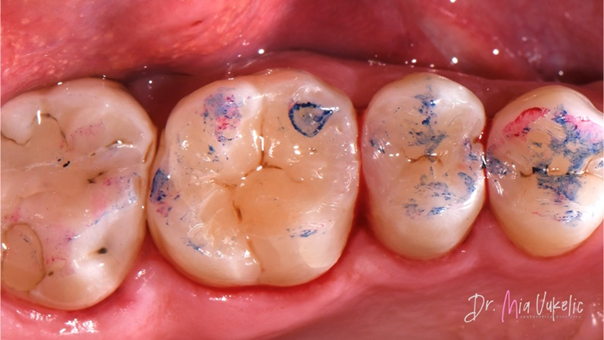

De hechtprocedure bestond uit een voorbehandeling van het glazuur met 35% fosforzuurgel (Ultra-Etch™-etsmiddel, Ultradent Products) volgens de selectieve etstechniek gedurende 15 seconden.

Na 30 seconden spoelen met water werd een tweecomponenten-adhesiefsysteem (Clearfil™ SE Bond, Kuraray*) toegepast. Eerst werd de primer aangebracht, gevolgd door het hechtmiddel en uitharding daarvan met een snoerloze VALO™-polymerisatielamp (Ultradent Products).